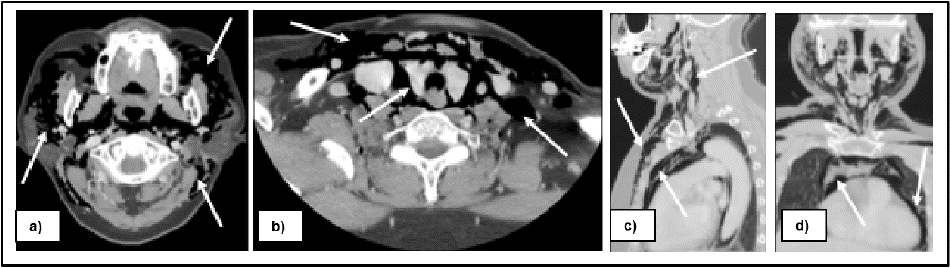

A head, neck and chest computed tomography (CT) scan was performed to assess the head, neck and thoracic region. The imaging revealed the extensive subcutaneous emphysema involving the bilateral temporal regions and deep cervical spaces, including the masticatory, parotid, parapharyngeal, retropharyngeal, and carotid spaces, with extension into the mediastinum and pericardium spaces, however there is no significant airway narrowing was noted (Figure 2).

Figure 2: Head, neck and chest CT scan presented severe emphysema involving the bilateral facial spaces and deep cervical spaces, including the masticatory,

parotid, parapharyngeal, retropharyngeal, and carotid spaces, with extension into the mediastinum and pericardium spaces.